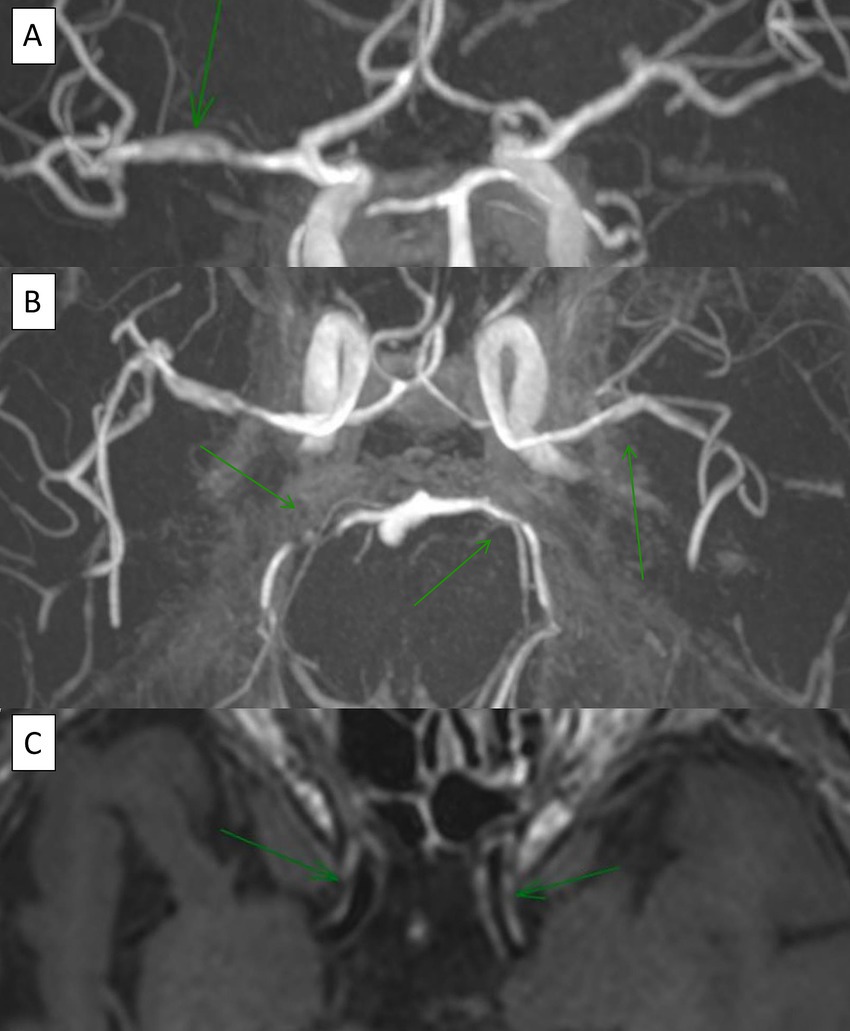

VWI showed wall enhancement of the main and smaller trunks of the circle of Willis (Figure 4), with segmental vascular irregularities visualized on TOF in 4 PACNS patients and 2 SACNS (p = 0.37) Further details and biopsy correlation (when available) are provided in the Supplementary Table 2. For PACNS, VWI positive findings were reported in one case of small, one case of mediumand two cases of a combination of small and medium-vessel vasculitis. Interestingly, in one patient with PACNS there was a negative biopsy with positive VWI imaging and another patient had negative VWI imaging but positive biopsy (small-vessel involvement and lymphocytic pattern) (Supplementary Table 2). For SACNS, 2 patients presented with positive findings (large-vessel vasculitis) and 2 patients presented with negative findings (one small-vessel and one large-vessel vasculitis), but no brain biopsies were available.

Figure 4. A 70-year-old patient with medical history of multiples acute ischemic stroke. Time-of-flight (TOF) brain MRI reveals multiple intracranial stenoses (A, coronal view; B, axial view), while vessel wall MRI (VWI) demonstrates circumferential contrast enhancement (C, axial view).

The main parameters of interest in VWI are concentric wall thickening and vessel-wall enhancement (VWE) (24). Concentric wall thickening, although highly prevalent in patients with PACNS, can also be observed in reversible constriction syndrome (RCVS) and other pathologies (45). VWE is not specific for PACNS, as it has been detected in normal vessel segments of PACNS patients (46), other pathologies (24) and even in healthy controls (47). Additionally, the rate of arterial stenosis co-localizing with VWE varies (22, 45, 48). Despite promising results, the use of VWI remains limited and debated. The lack of standardized protocols, hardware differences, and variable timing with respect to diagnosis or treatment have hindered its broader adoption. Further studies are needed to clarify its accuracy across vessel sizes and histological patterns in PACNS. In our cohort, both PACNS and SACNS, we found negative results in case of small-vessel angiitis and positive findings in case of medium/large-vessel angiitis. In particular, within our cohort of PACNS, one patient had a positive VWI and negative biopsy (likely due to medium-size vessel involvement, that was not sampled) while another patient had a negative case of VWI and a positive biopsy (Figure 3), presumably reflecting very small-vessel involvement below the resolution of MRI. This confirms an inverse relationship between the size of the vessel involved and VWE, consistent with previous findings (22, 49), which demonstrate less frequent abnormalities in small-vessel angiitis or biopsy-diagnosed cases.